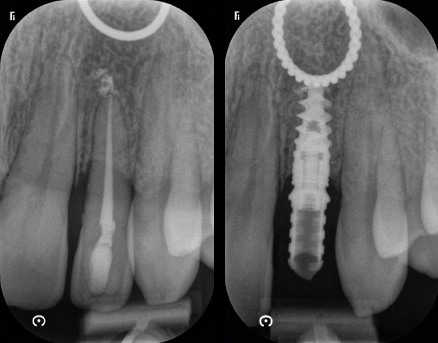

Cas esthétique d'implant unitaire

Mise en charge immédiate

Avec un implant unitaire et la mise en charge immédiate dans les zones esthétiques (quand c’est possible et selon le cas observé), la phase de cicatrisation, normalement de quelques semaines, se déroule avec une dent provisoire fixe (couronne provisoire vissée) qui permet d’éviter l’installation d’une prothèse provisoire amovible (dentier). Cela épargne aux patients de subir une intervention supplémentaire et il s’agit aujourd’hui d’une procédure standardisée, très confortable et très appréciée par les patients. C’est uniquement dans les cas exceptionnels, comme par exemple en cas d’infections aiguës, qu’il est préférable d’extraire d’abord la dent délabrée et de poser l’implant seulement lorsque l’inflammation est résolue.